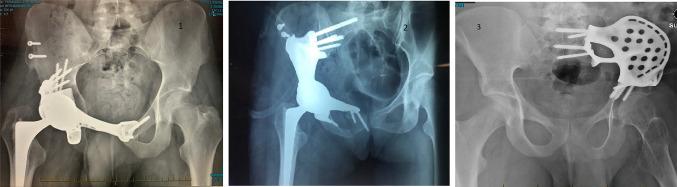

Access to custom 3D printed pelvic implants (3DPI) is improving for application in both arthroplasty revision and tumour reconstruction. There is limited evidence regarding the safety and outcomes of such implants for large bony defects of the pelvis. The aim of this study is to report the incidence of complications, patient mortality and implant survival following pelvic reconstruction using custom 3Dprinted prostheses in the setting of extensive pelvic bone defects following pelvic tumour resection or failure of total hip arthroplasty (THA).

One hundred and six procedures were completed (Revision THA = 33; Tumour Pelvis = 73) with a median follow up of 4.1 years, ranging from 0.6 to 10 years. Acetabular loosening was the most frequent indication for the Revision THA cohort, while indications for tumour varied across primary presentations, metastases and failures of previous resection/reconstruction. Intraoperative complications were observed in 4.1% (95%CI 1.1-12.3) of Tumour Pelvis cases. Overall implant retention was 96% (90-99). No mortality events were observed in the Revision THA cohort, with 5-year patient survival 79% (70-90) in the Tumour Pelvis cohort. Procedure-survival free from periprosthetic infection was 86% (74-100) in the Revision THA cohort and 85% (76-95) in the Tumour Pelvis cohort. Modelling adverse events using multistate survival models in both cohorts revealed complex time-varying presentation of adverse events, with a significant burden of reoperations and local tumour recurrence in the Tumour Pelvis cohort.

3DPIs are a safe and viable option for complex reconstruction of the pelvis across a range of oncological and non-oncological indications. The initial results of the present study provide important information to aid in counselling patients about such procedures and allocating healthcare resources for ongoing care. Further work is required to document functional and biomechanical outcomes in these patient populations.

定制3D打印骨盆植入物(3DPI)在关节置换翻修术和肿瘤重建中的应用越来越广泛。关于此类植入物用于骨盆大骨缺损的安全性和效果的证据有限。本研究的目的是报告在骨盆肿瘤切除或全髋关节置换术(THA)失败后出现广泛骨盆骨缺损的情况下,使用定制3D打印假体进行骨盆重建后并发症的发生率、患者死亡率和植入物存活率。

共完成了106例手术(翻修THA = 33例;肿瘤骨盆 = 73例),中位随访时间为4.1年,范围从0.6年至10年。髋臼松动是翻修THA队列中最常见的指征,而肿瘤患者的指征因原发表现、转移和既往切除/重建失败而有所不同。在4.1%(95%CI 1.1 - 12.3)的肿瘤骨盆病例中观察到术中并发症。总体植入物保留率为96%(90 - 99)。在翻修THA队列中未观察到死亡事件,肿瘤骨盆队列中5年患者生存率为79%(70 - 90)。翻修THA队列中无假体周围感染的手术生存率为86%(74 - 100),肿瘤骨盆队列中为85%(76 - 95)。在两个队列中使用多状态生存模型对不良事件进行建模,结果显示不良事件呈现复杂的随时间变化情况,肿瘤骨盆队列中再次手术和局部肿瘤复发的负担较重。

3DPI是一种安全可行的选择,可用于一系列肿瘤和非肿瘤指征的骨盆复杂重建。本研究的初步结果提供了重要信息,有助于为患者提供此类手术的咨询,并为持续护理分配医疗资源。需要进一步开展工作以记录这些患者群体的功能和生物力学结果。